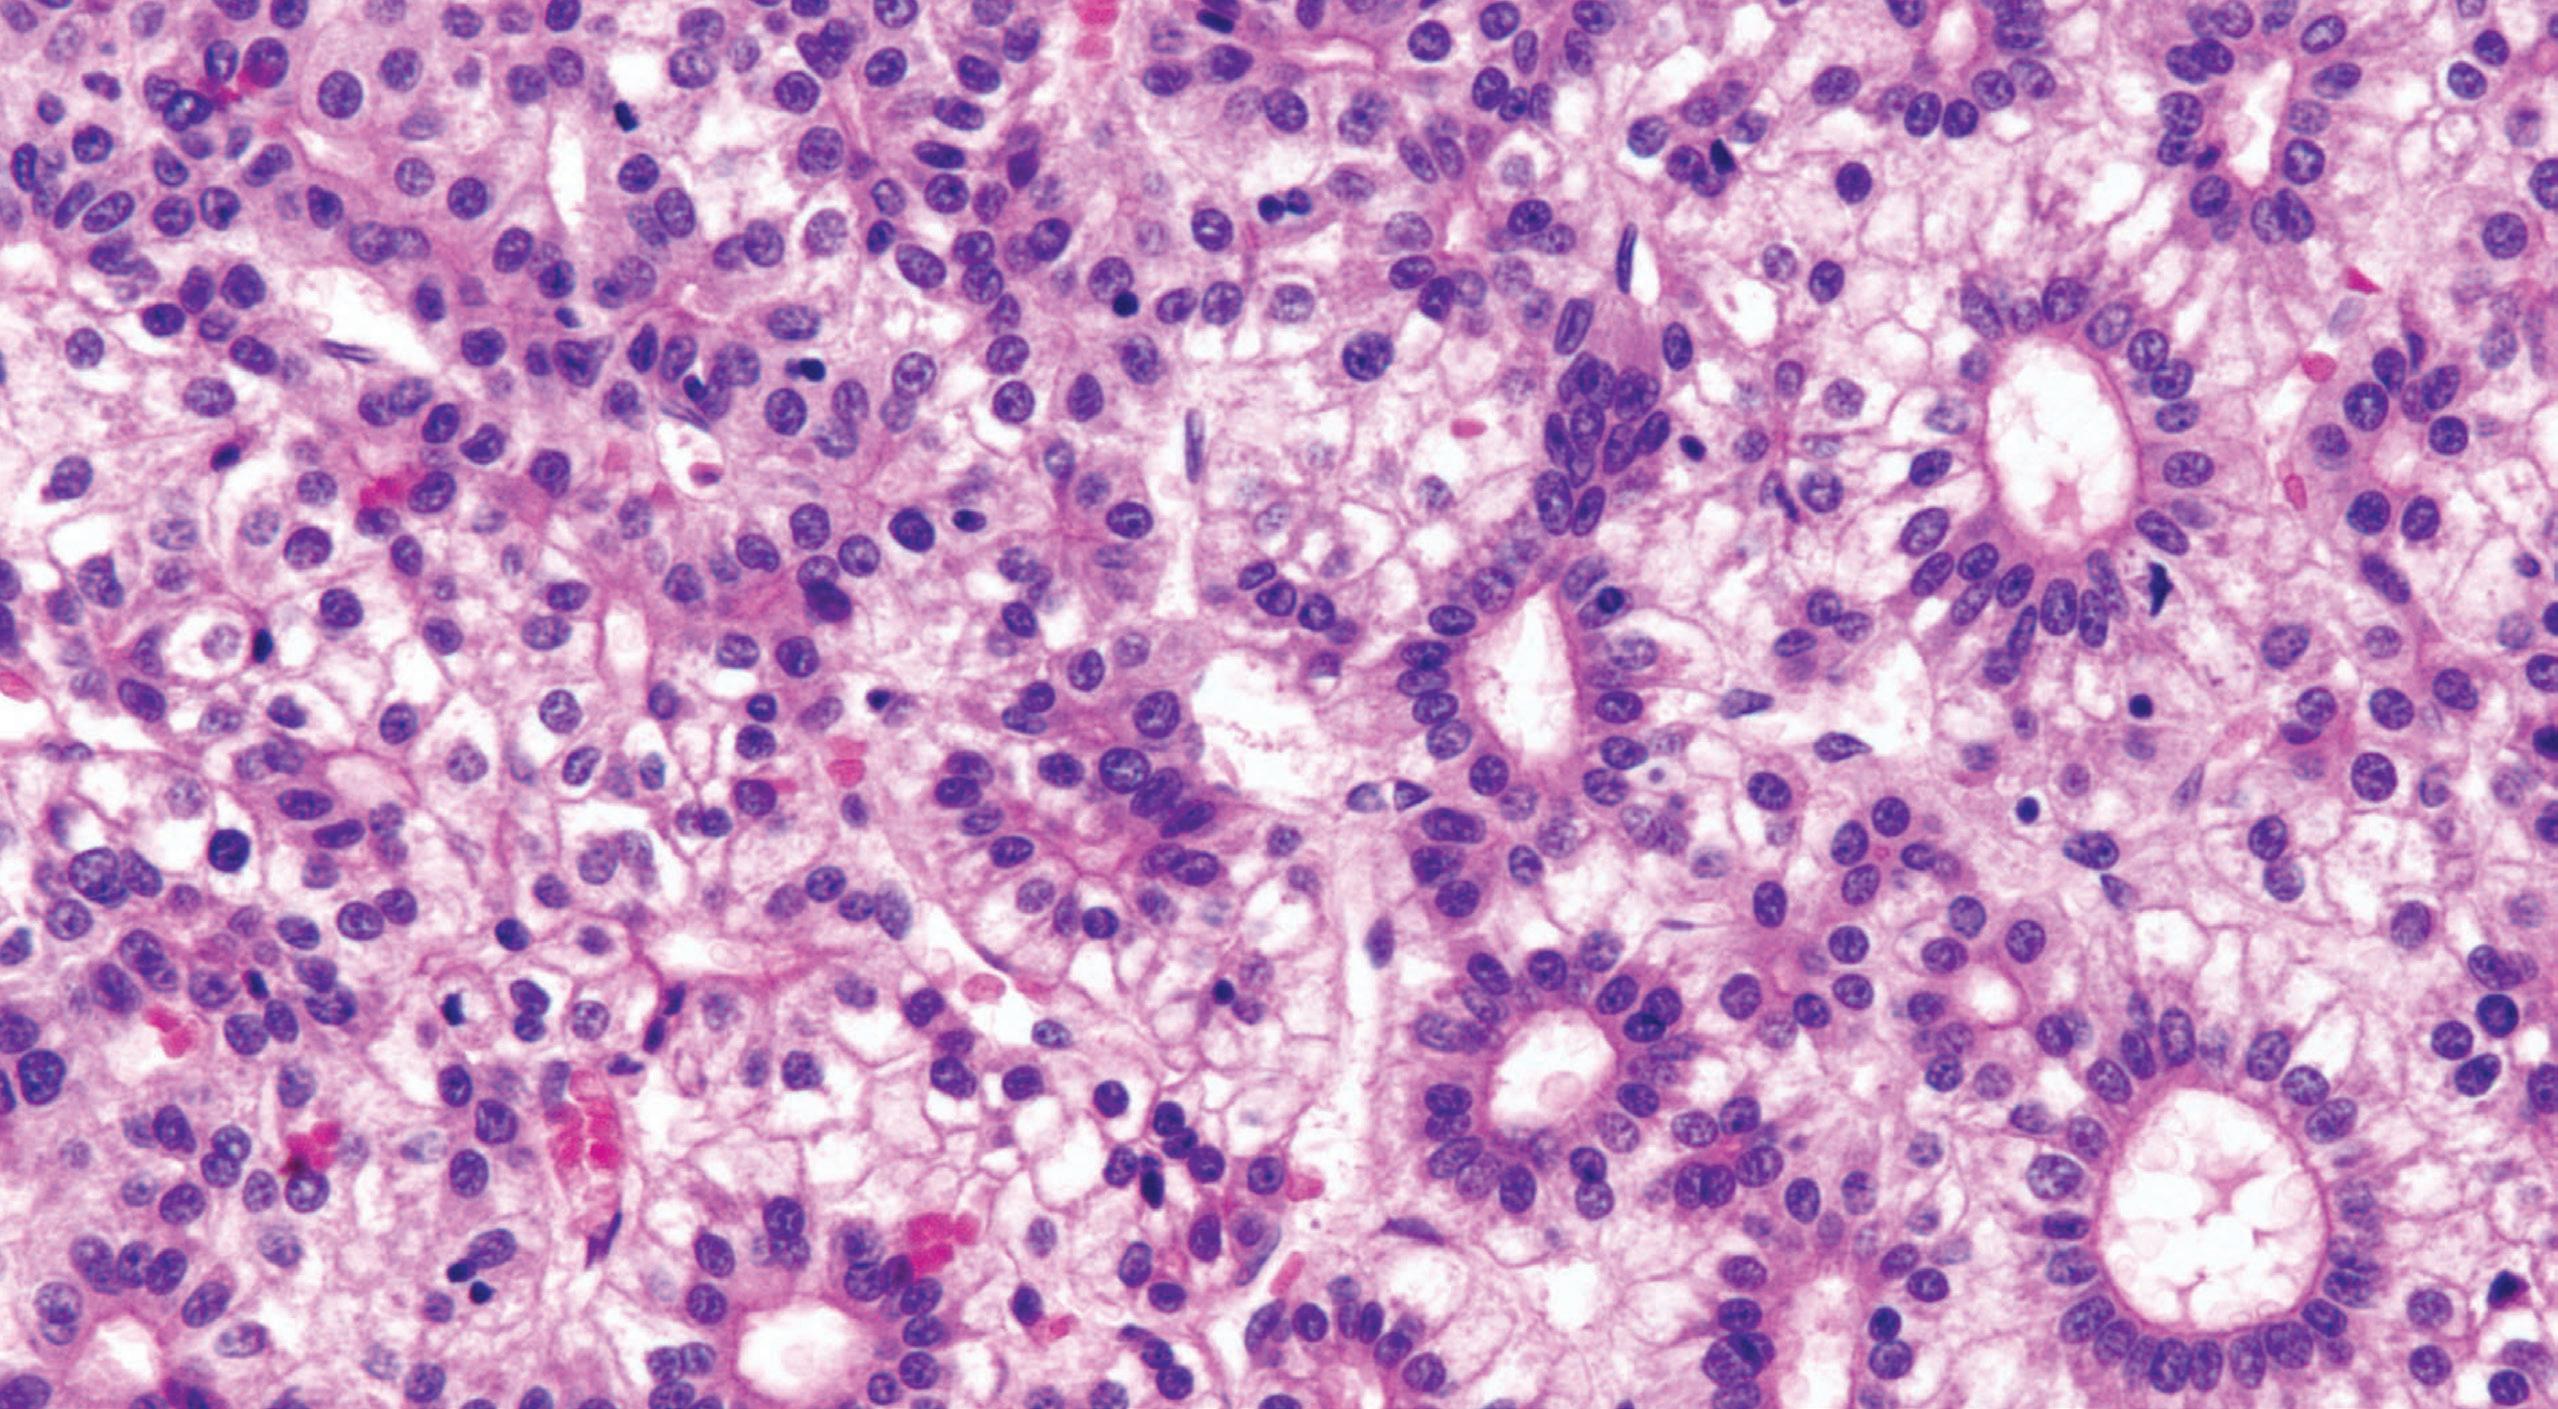

MiCRosCopiC findings

Biopsies show increased intraepithelial eosinophils (≥15 eosinophils/hpf) with concentration of eosinophils toward the luminal aspect of the epithelium (superficial layering). Eosinophilic microabscesses and degranulation of eosinophils (Fig. 1.8) are frequently present. The density of eosinophils can vary with anatomic location of biopsy and within biopsy fragments. In general, biopsies from the proximal segment reveal more eosinophilia than the distal segment. It is therefore recommended that the total number of eosinophils per high-power field

be generated by examining the fragments at low magnification and selecting the high-power field with maximum number of eosinophils (Fig. 1.9). Care should be taken to avoid counting eosinophils within the papillae. Other findings include basal cell hyperplasia, elongation of the papillae to greater than 50% the thickness of the squamous epithelium, spongiosis, lamina propria, and submucosal fibrosis. In patients who have received diet elimination or steroid therapy, follow-up biopsies may be performed to evaluate response to therapy, in which case, giving the exact eosinophil count may be helpful.

Eosinophilic esophagitis. intense eosinophilic infiltrate.

Eosinophilic esophagitis. intraepithelial eosinophils (>20/hpf).